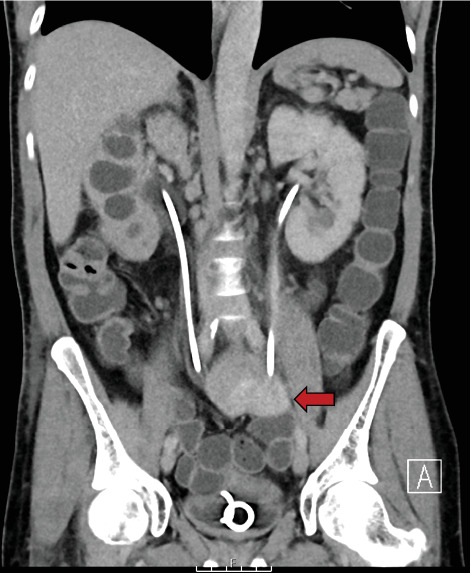

Background: Ureteric small bowel fistulas are rare entities, with limited reports in the literature. These pathological connections between the ureter and small bowel can lead to recurrent upper urinary tract infections and pose significant diagnostic and therapeutic challenges. The primary cause of ureteric small bowel fistula formation is iatrogenic intervention, such as percutaneous nephrolithotomy (PCNL) or abdominal surgery involving tissue resection. However, they can also arise spontaneously due to local chronic inflammation and infection. Given their rarity, there is no standardised management pathway, and the treatment approach should be individualised. Case Presentation: We present the case of a 57-year-old man presenting with a history of extensive locally advanced distal sigmoid carcinoma, managed with Hartmann's procedure with end colostomy followed by adjuvant radiotherapy and chemotherapy. He later developed a mid-ureteric small bowel fistula, presenting with urosepsis, a high-output stoma, deteriorating renal function and severe metabolic acidosis. Conservative management with regular ureteric stent exchanges every 3-4 months has successfully preserved renal function and improved his quality of life. Surgical closure was not pursued due to high operative risk, and repeat imaging has shown no evidence of persisting fistula, suggesting possible spontaneous closure. Conclusion: The treatment options for this ureteric small bowel fistula were limited. A lifelong nephrostomy was deemed unsuitable due to incompatibility with the patient's profession, and surgical intervention was associated with significant complexity due to the patient's history of malignancy and radiotherapy-related tissue changes. Therefore, a conservative strategy involving serial ureteric stent exchanges was pursued. Early recognition and individualised treatment of ureteric-enteric fistulas are essential, as timely intervention can significantly enhance prognosis and quality of life.

Abstract Image